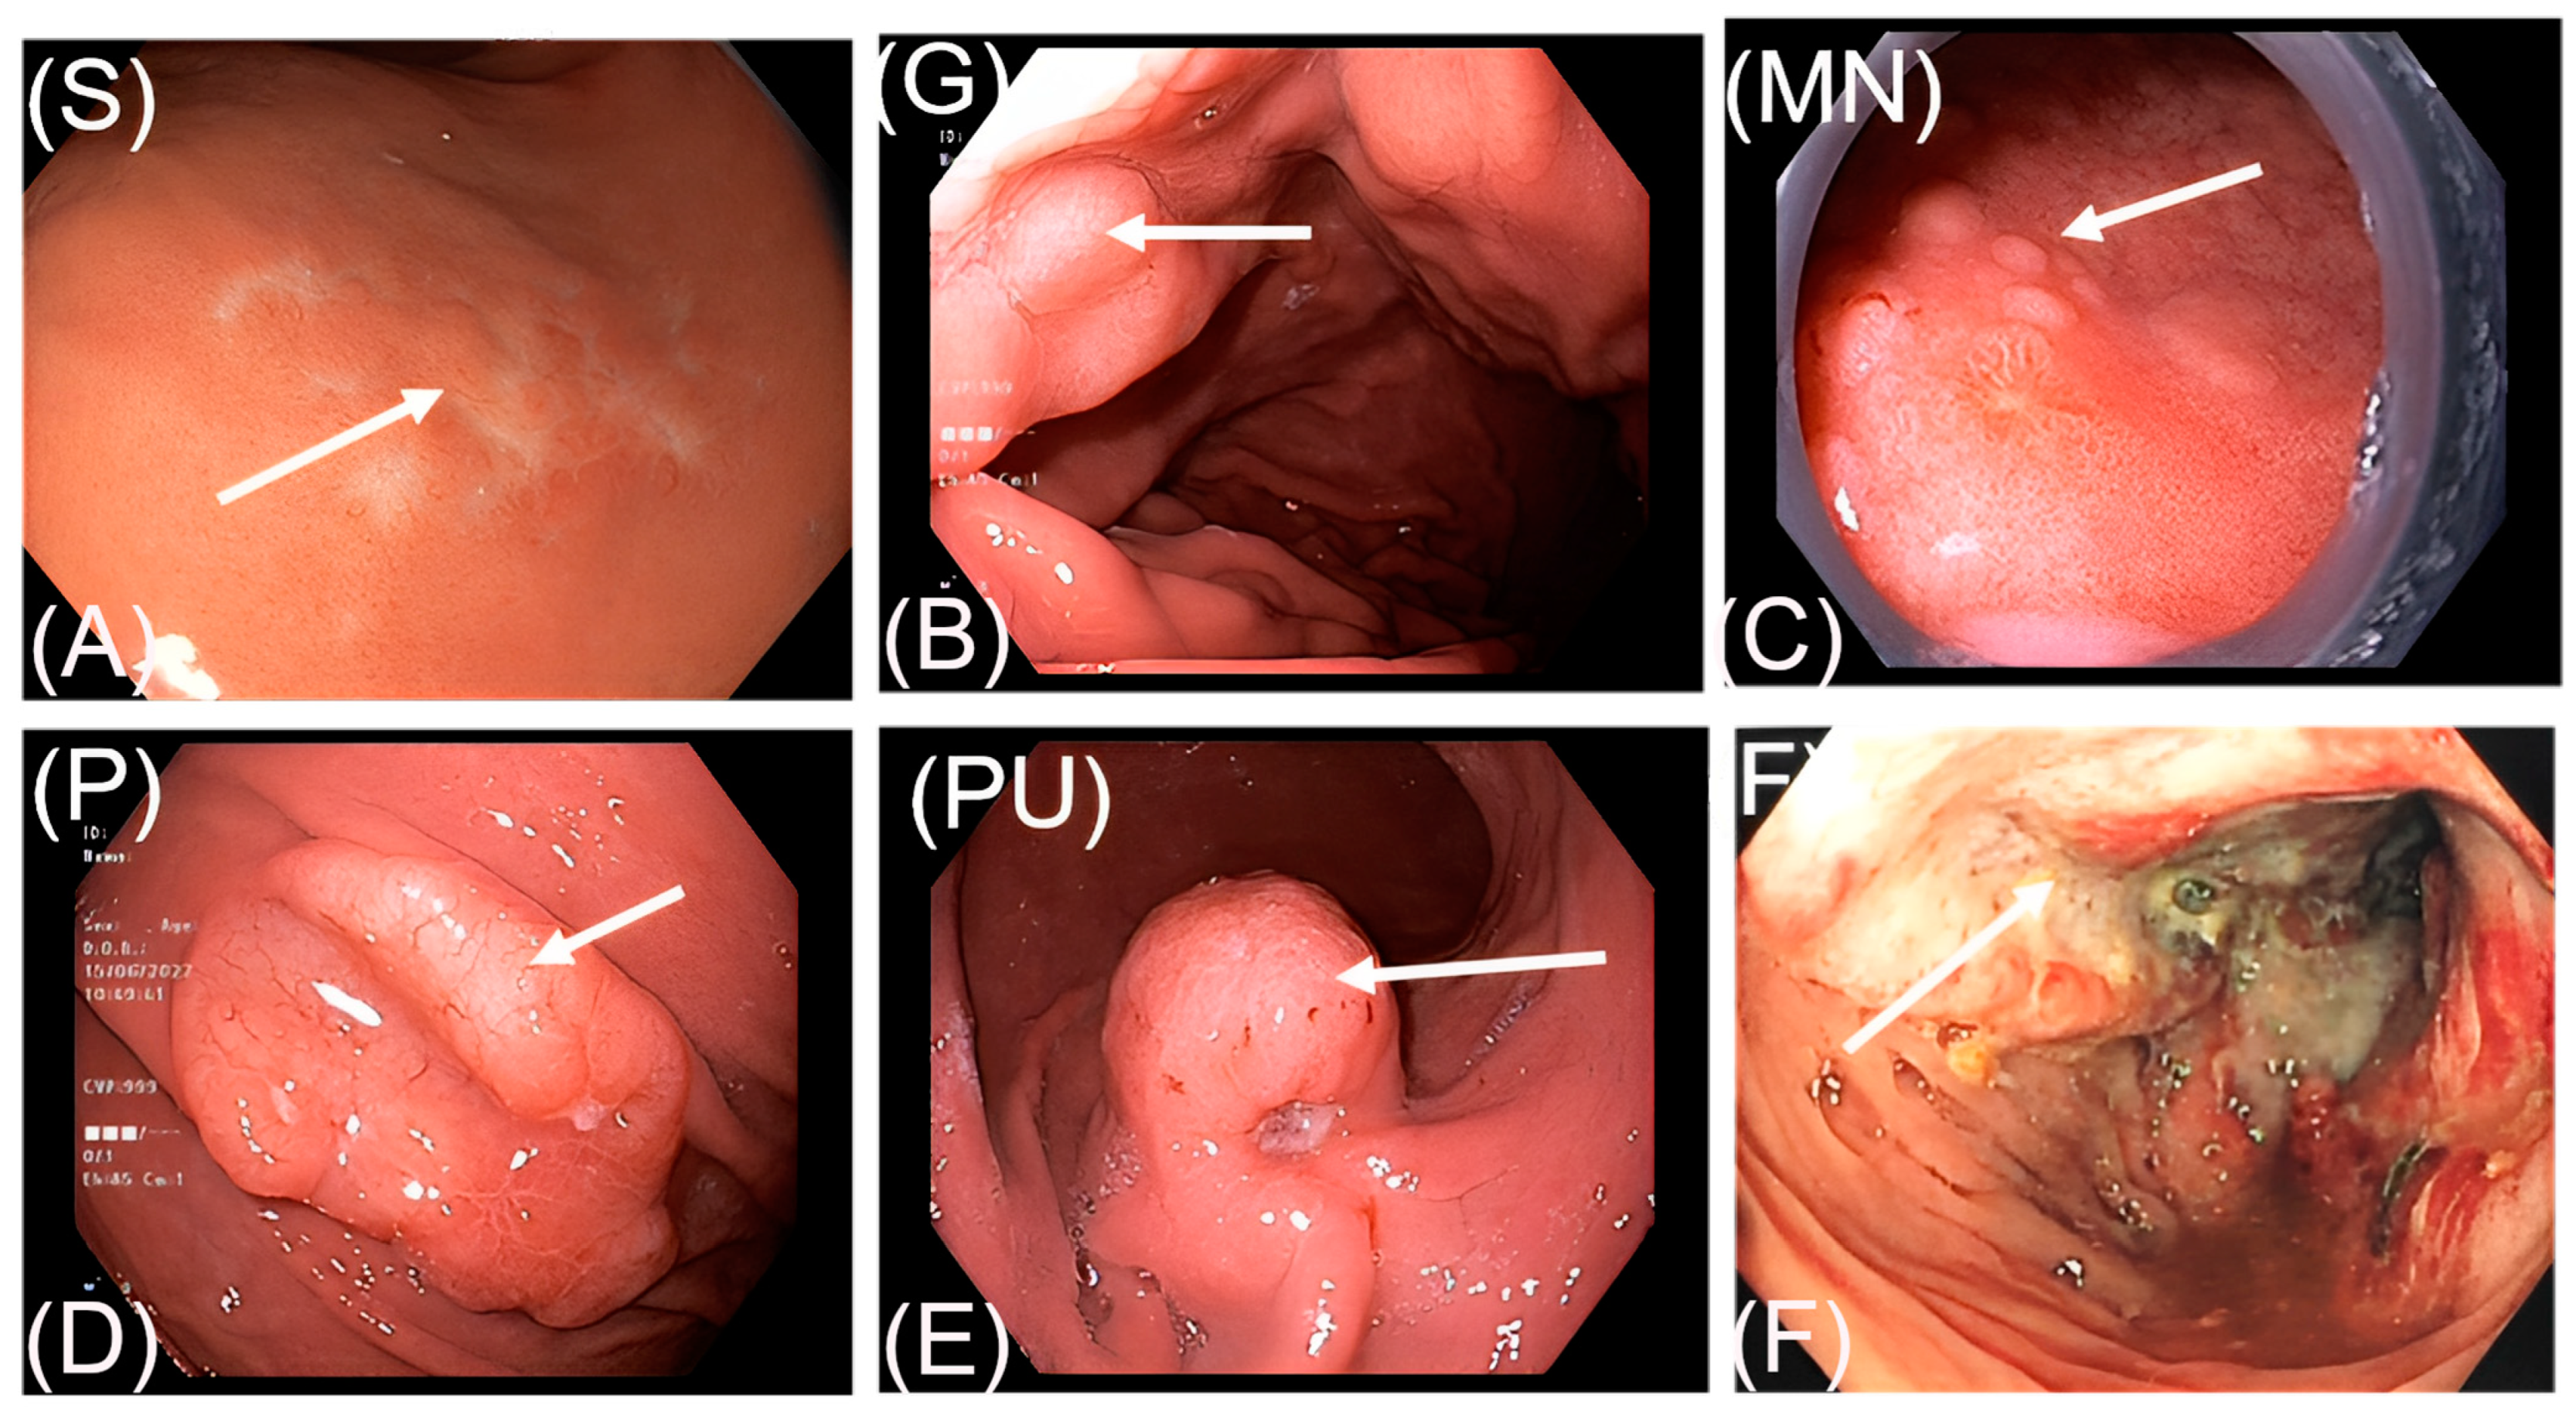

3.2. Endoscopic Findings

| Endoscopic Features | Case Number | % |

|---|---|---|

| S | 72 | 51.4 |

| P | 29 | 20.7 |

| F | 18 | 12.9 |

| PU | 13 | 9.3 |

| G | 5 | 3.6 |

| MN | 3 | 2.1 |

| Total | 140 | 100.0 |